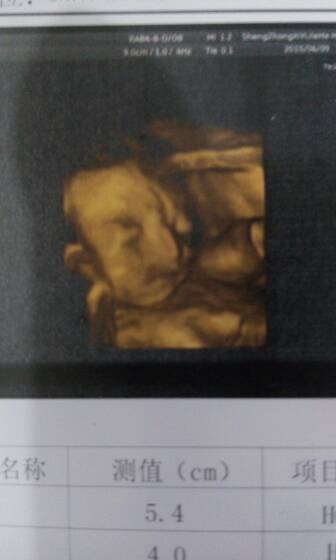

眉毛是不是不好看!像倒八字还能长好吗? 眉毛是不是不好看!像倒八字还能长好吗? 点击展开 158*****331_NIWu 2015-06-09 18:39 为您推荐: 其他回答 祝宝妈好孕 &丶温瞳\Triste 2015-06-09 20:24 生下来就知道了,, 城熙麻麻@ 2015-06-09 19:50 出来才知道 短发菇涼萌妹子i 2015-06-09 19:29 祝宝妈好孕 153*****620_OIhk 2015-06-09 19:01 嗯嗯。谢谢 记忆╰爱过后的破损╮。 2015-06-09 18:48 加载更多 相关问题 倒八字的眉毛 走路外八字,特别不好看 你们会不会觉得女孩子走路外八字不好看